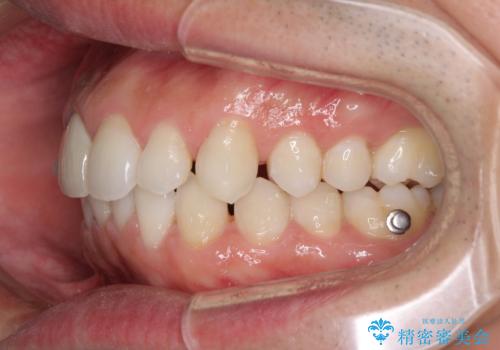

- 口の閉じにくさを気にして来院された患者様です。

患者様と相談の上、横顔の印象から抜歯矯正は必要ないと判断し、IPR(歯と歯の間)並びに歯列全体の後方移動により口元の突出感の改善することとしました。

しっかりと装着時間を守り、ゴムかけも徹底していただいたので、思いの外口元を引っ込めることができました。

これ以上の改善を望まれましたが、非抜歯矯正でこれ以上口元を引っ込めると食いしばりすやすい咬合となるため、この歯列で終了としました。